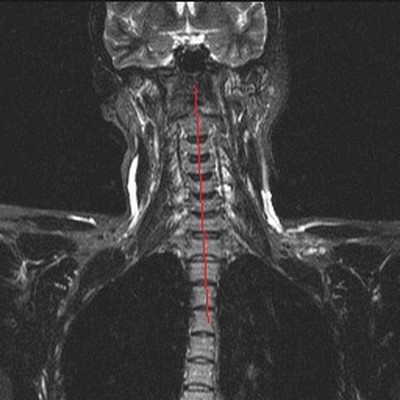

МРТ позвоночника в шейном отделе, оценка высоты дисков (указана красными линиями)

На сериях МРТ, выполненных в аксиальной, корональной и сагиттальной плоскостях, взвешенных по Т2-ВИ, Т1-ВИ и STIR-ИП, получены изображения шейного отдела позвоночника.

Определяется патологический кифоз с вершиной на уровне тел позвонков С5-С6.

Выявляются дегенеративно-дистрофические изменения в виде умеренно выраженного понижения интенсивности сигнала от межпозвонковых дисков в сегментах С2-Th1, со снижением высоты в сегментах С5-С7, а также формирования передних и заднебоковых краевых костных разрастаний. Унковертебральный артроз на уровне сегментов С5-С7.

В смежных отделах позвонков С6-С7 определяются зоны гиперинтенсивного МР-сигнала на Т2-ВИ, STIR-ИП и гипоинтенсивного в Т1-ВИ (вероятно, обусловленные отёком вещества костного мозга).

Определяются неровности смежных замыкательных пластин тел позвонков С5-С7 за счет хрящевых узлов Шморля.

В сегменте С3-С4 под краевыми остеофитами определяется дорзальная медианная протрузия межпозвонкового диска, размером до 2,5мм. Переднее субарахноидальное пространство деформировано. Межпозвонковые отверстия умеренно сужены, достоверных данных за компрессию корешков нервов не выявлено. Передне-задний размер позвоночного канала до 14мм.

В сегменте С5-С6 под краевыми остеофитами определяется задняя диффузная протрузия межпозвонкового диска, размером до 2,5мм. Переднее субарахноидальное пространство деформировано. Межпозвонковые отверстия умеренно сужены, достоверных данных за компрессию корешков нервов не выявлено. Передне-задний размер позвоночного канала до 13мм.

В сегменте С6-С7 под краевыми остеофитами определяется задняя диффузная протрузия межпозвонкового диска, размером до 2мм. Переднее субарахноидальное пространство деформировано. Межпозвонковые отверстия умеренно сужены, достоверных данных за компрессию корешков нервов не выявлено. Передне-задний размер позвоночного канала до 14мм.

Сигнальные характеристики от шейных позвонков не изменены.

Видимые отделы спинного мозга в размерах не увеличены, имеют четкие контуры и однородную структуру, интенсивность МР сигнала не изменена.

Паравертебральные мягкие ткани не изменены.

МР-признаки дегенеративно-дистрофических изменений шейного отдела позвоночника с нарушением статики. Протрузии дисков на уровне сегментов С3-С4, С5-С6, С6-С7. Унковертебральный артроз. Хрящевые узлы Шморля смежных замыкательных пластин тел позвонков С5-С7.